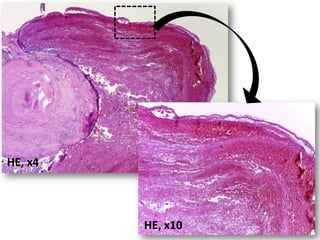

Uma mulher de 72 anos apresentou um nódulo assintomático na mucosa labial inferior há cerca de três meses. Após biópsia, o diagnóstico foi de flebólito, descartando as hipóteses iniciais de miofibroma ou neurofibroma.

• Paciente dosexo feminino, 72 anos de idade; e

que apresenta nódulo bem delimitado

assintomático em mucosa labial inferior com

evolução de cerca de três meses.